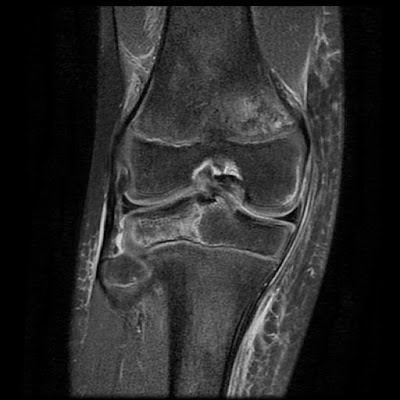

Acl and mcl injuries associated with lateral plateau fracture. Fractures of the tibial plateau affect knee motion, stability, and alignment. Avulsion fracture of margin of lateral tibial plateau just below joint line.

This is an avulsion fracture of the lateral tibial condyle immediately beyond the articular surface with the knee.

The lateral plateau is involved 93% of the time but the medial plateau. In patients without displacement of the. Pathology the most common mechanism of injury involves axial loading, e.g. Type iii are rim avulsion fractures. A tibial plateau fracture generally results from trauma to the upper part of your shin. Avulsion fractures commonly occur in children and adolescents, with 50 the goal of tibial plateau fracture treatment is joint stability, with articular congruity and normal alignment. Tibial plateau fractures are a common orthopedic injury. Tibial tuberosity avulsions combined with lateral tibial plateau in an adolescent are rare injuries. Rim avulsion fracture of lateral plateau. The first is by a medial or lateral based force (such as the so called bumper fracture when a car's bumper strikes the outside of a person's leg creating a valgus, or inward, force across the knee). Fractures of the tibial plateau affect knee motion, stability, and alignment. Symptoms include pain, swelling, and a decreased ability to move the knee. Associated with tear of acl and meniscal ligaments. He was treated with open surgical reduction and internal fixation. Ly, md ohio state university. The lateral plateau is involved 93% of the time but the medial plateau. Tibial plateau fractures were originally termed a bumper or fender fracture but only 25% of tibial plateau fractures result from impact with automobile bumpers.